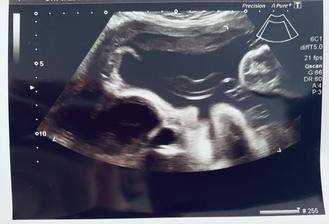

15.7. KO+odběry 9+6tt - na ultrazvuku vše úplně v pořádku, miminko už je krásný malý medvídek ♥ Krásně povyrostlo a odpovídá místo 9+6tt dokonce 10+3tt! Museli jsme kvůli tomu i změnit datum screeningu na 30.7. Dostala jsem těhotenskou průkazku a termíny dalších kontrol. Velikost miminka je 35,4mm. Sestřička odebrala krev, zkontrolovala moč, všechno se zdá být úplně v pořádku.